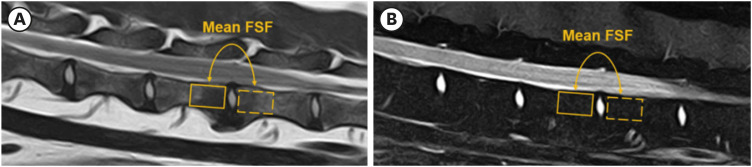

Methods: IVD degeneration in dogs was classified morphologically using the Pfirrmann grade, and the vertebral body FSF was evaluated quantitatively.

Results: The vertebral body FSF showed a statistically significant difference among the age groups. The vertebral body FSF was significantly higher in Pfirrmann grades 3-5 than in grades 1 and 2. The mean Pfirrmann grade of CD dogs was higher than that of NCD dogs in the four-to-six-year-old group. The mean vertebral body FSF of CD dogs was higher than that of NCD dogs in the group of seven years and above.